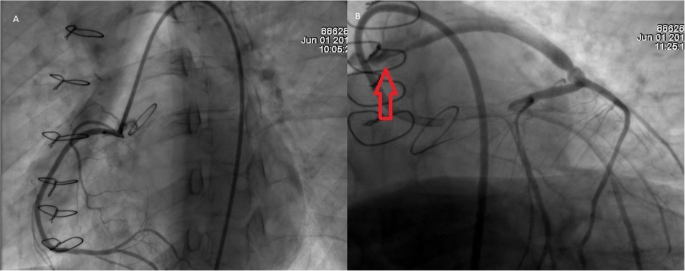

Nonetheless 3 months after surgery she suddenly experienced acute chest pain, shortness of breath, nausea, and fatigue thus was brought immediately to the emergency room. On clinical examination, a tachycardic and diaphoretic patient was encountered. An electrocardiogram (EKG) detected an anterior myocardial infarction with ST-elevation, along with troponin values above 130 pg/L and INR of 2.27. Femoral access was achieved, and percutaneous coronary intervention was decided. On coronariography, (Fig. 4a, b) the right native coronary artery appeared normal and to our surprise it recanalized spontaneously. However, the left coronary artery occlusion persisted and there was a severe thrombotic stenosis of the left saphenous vein bypass. The right saphenous vein bypass to the right coronary artery was also totally occluded. After successful intraortic balloon pump (IABP) insertion a stent was placed on the saphenous vein graft achieving adequate blood flow improving the patient’s condition. Transthoracic echocardiogram revealed anterolateral hypokinesia of the left ventricle, with an ejection fraction of 45%. After this procedure, the patient fully recovered and had no cardiac symptoms. She was discharged under close anticoagulation surveillance. Three months later and due to the fact that the patient had experienced early graft failure and her young age, it was decided to perform percutaneous revascularization of the main left coronary trunk which was performed successfully (Fig. 5a) with intravascular ultrasound guidance. She completely recovered from the procedure and 1 year after surgery on regular follow-ups, the patient is doing well without any complications.